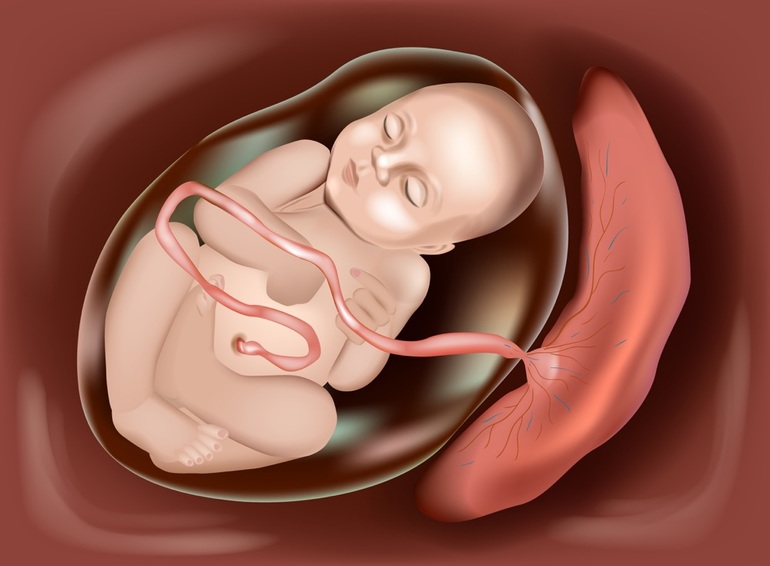

Околоплодный пузырь и плацента: структура и функции